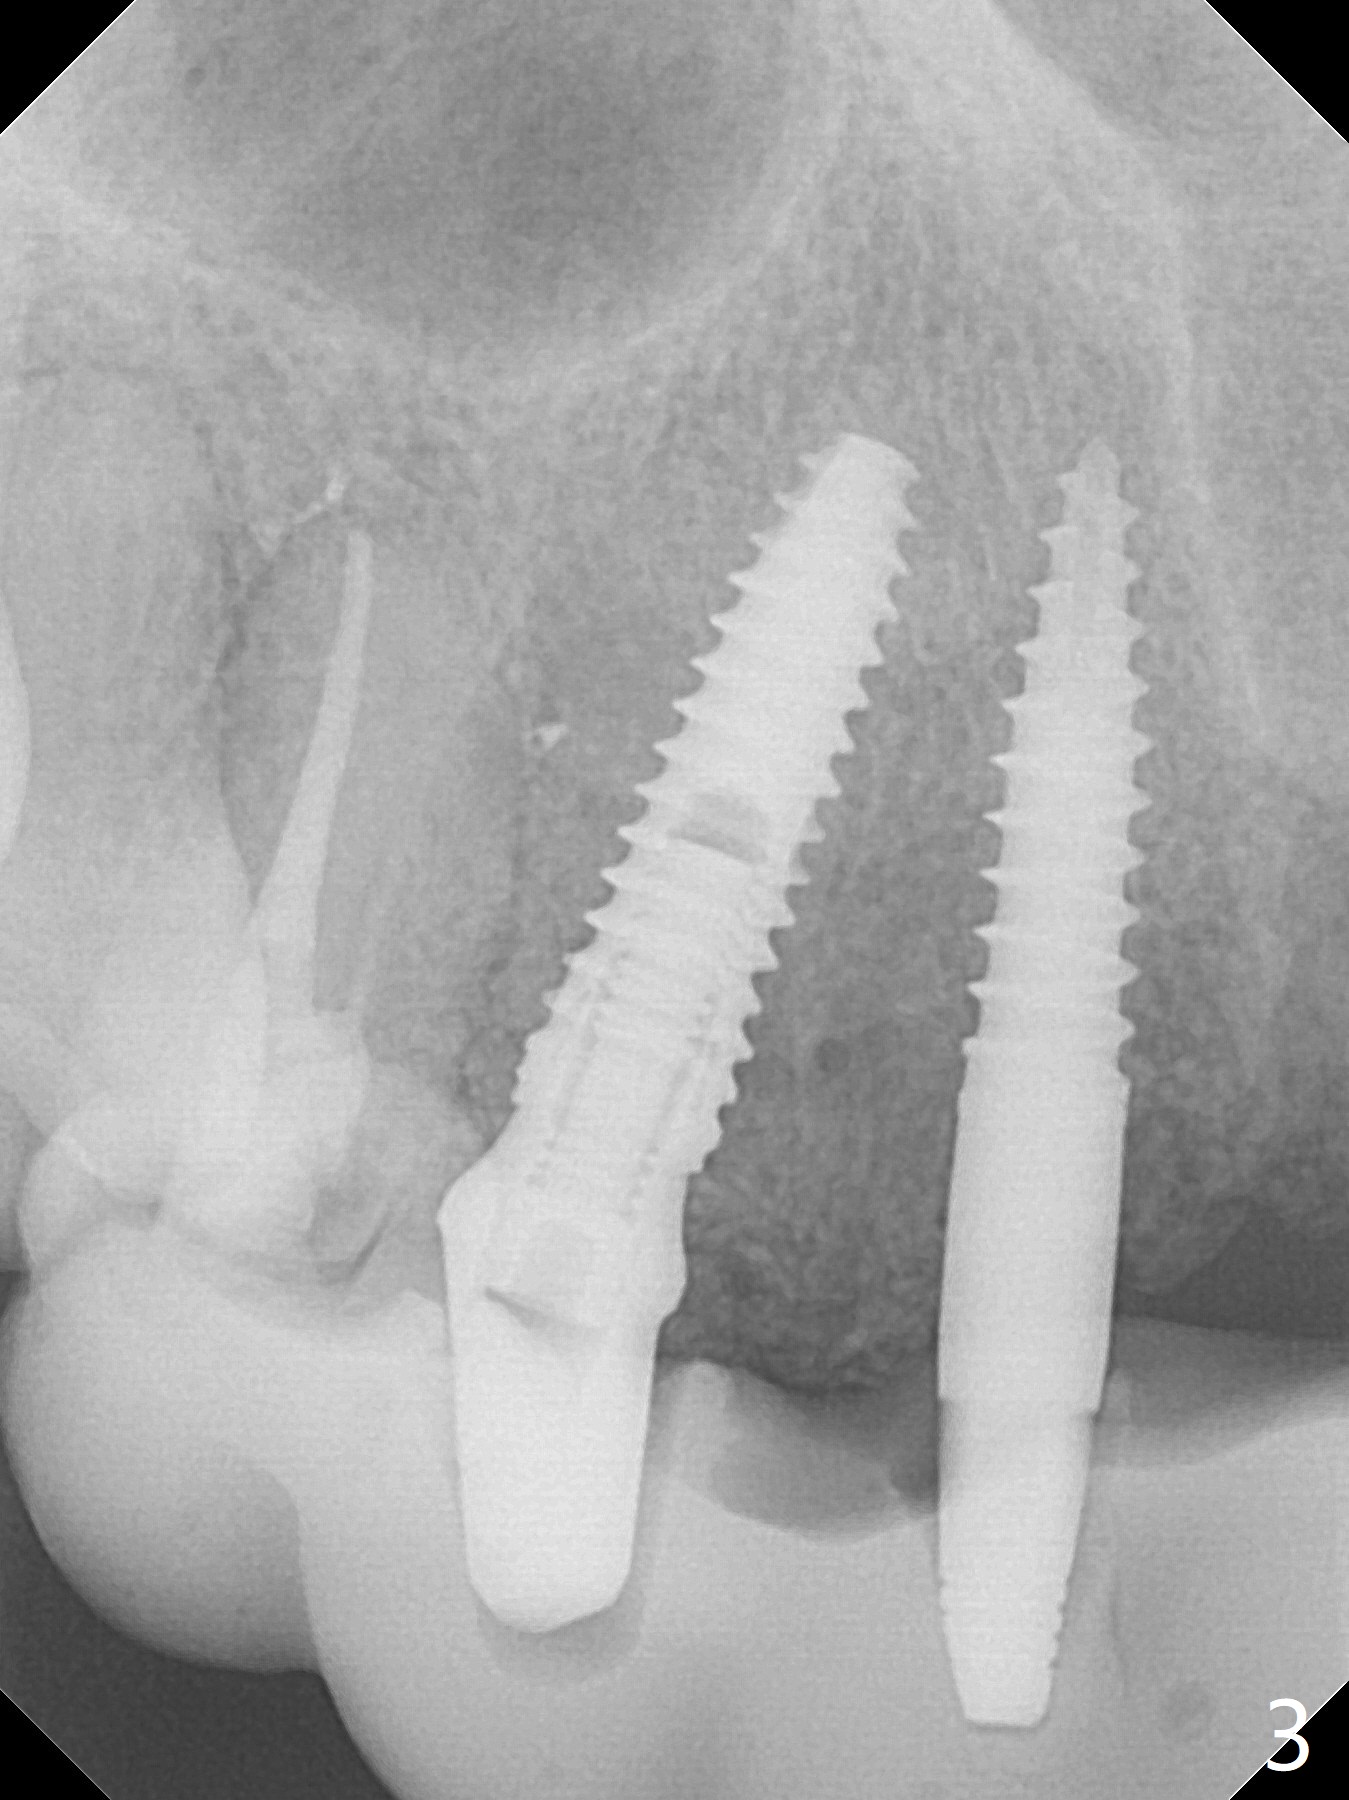

It is smooth and quick to finish osteotomy with guide at #6,7,10-12, but when 3 mm 1-piece implants are placed free hand at #7 and 10 (Fig.1,2), the gingival parts of the abutments contact the incisal edges of the lower incisors (anterior deep bite) in spite of effort to change the trajectory by repeated back and forth placement after use of Lindamann bur buccally. Following an immediate provisional (Fig.3,4), the occlusal surface of the posterior teeth are raised to eliminate anterior restoration interference. Immediate postop CBCT shows that the implants at #7 and 10 could be placed more buccally (Fig.6,7, as compared to the normal position at #6,11,12 (Fig.5,8,9)). Fig.10 was taken 2 days preop, while Fig.11-13 postop. Can we change 1-piece implants (3mm) at #7 and 10 to 2-piece one (3.5) and use angled or cementation abutments for easy restoration (Fig.14-16)?